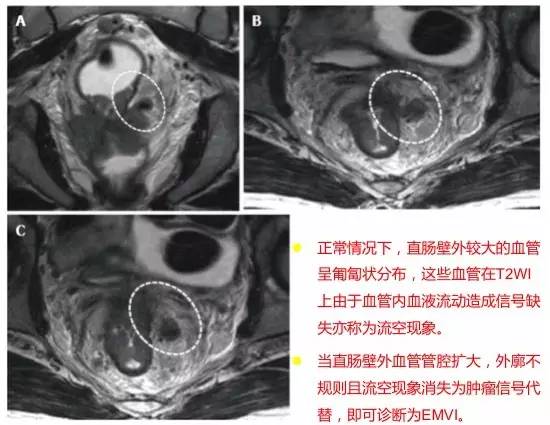

壁外血管侵犯 EMVI

多达一半的结直肠癌病例发生 EMVI,是局部复发、远处转移和较差 OS 的独立危险因素。EMVI 是在直肠固有肌层以外直肠系膜的血管内存在恶性细胞。MR 成像描绘的 EMVI 的严重程度与 DFS 相关。

EMVI 的诊断线索:

1. 根据定义,EMVI 必须与至少 T3 类肿瘤有关。T1 或 T2 不具有侵入外部血管的潜力。

2. 只要肿瘤靠近血管,就应该考虑 EMVI 的可能性。

3. EMVI 的迹象:(1)在血管结构内存在肿瘤信号强度;(2)血管扩张;(3)肿瘤扩张通过和超出血管壁,破坏血管边界。

4. 最后,如果存在 EMVI,必须考虑所涉及静脉是否威胁到直肠系膜筋膜(即它们是否在筋膜的 1 mm 以内)。

图 33 EMVI 的示意图

图 34 EMVI

为了更为准确的判断 EMVI,根据肿瘤外形,肿瘤周围是否存在血管,受累血管管径、轮廓及信号的变化,MRI 评估直肠癌 EMVI 的 5 级评分系统,并将评分为 0~2 定义为阴性,3 和 4 的定义为 EMVI 阳性。